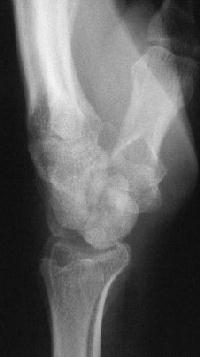

Clinical Example: Midcarpal instability following distal scaphoid excision

Distal scaphoid excision is gaining popularity as a treatment of scaphoid nonunion. It requires the strong radioscaphoid and radioscapholunate ligaments to maintain support of the remaining proximal carpus. In this case, the proximal carpus was destabilized by the effect of radial stylidectomy on these ligaments.

Clinically and by bone scan, this patient sustained a scaphoid fracture, but obviously had a preexisting distal pole cyst.

Intraoperatively, the distal pole cyst was eggshell thin with comminution into the ST joint. Stable fixation was not possible, even with a radial

styloid bone graft, and the distal pole was excised. Postoperatively, carpal instability was present.

This progressed...

Carpal tunnel developed and progressively worsened, probably related to the palmar prominence of the lunate. The patient underwent carpal

tunnel release and midcarpal fusion and returned to heavy manual work.